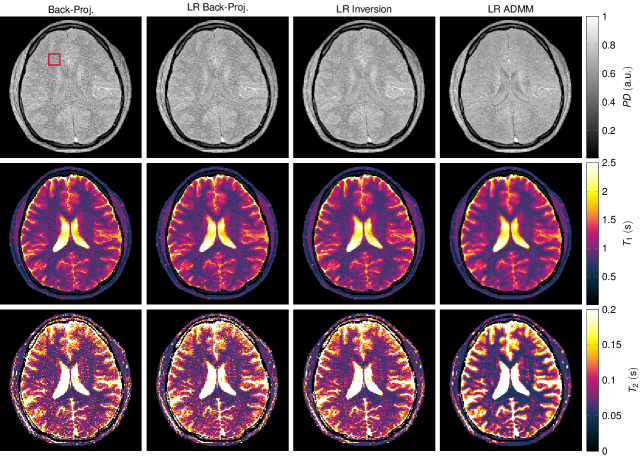

The corresponding quantitative maps are shown in Fig.ย 6. They were reconstructed with Eq.ย (7) (second column), (16) (column 3 and 4) and (18) (column 5). The back-projection reconstruction (column 2) exhibits significant undersampling artifacts in all three parameter maps. Noise-like artifacts can be seen in the proton density, as well as in the T1subscript๐‘‡1T_{1} map and most prominently in the T2subscript๐‘‡2T_{2} map. The quantitative maps reconstructed from the low rank back-projection (third column of Fig.ย 6) and the time domain back-projection (second column) are visually the same. In fact, the low rank back-projection does not promise improved image quality and is purely motivated by computation time (22). On the contrary, solving the inverse problem in the low rank approximation (Eq.ย (17)) results in significantly improved quantitative maps: The noise-like artifacts are reduced, which is even more the case when employing the ADMM algorithm in the low rank domain.

Figure 6

The displayed excerpts of quantitative maps compare the discussed reconstruction methods. The simulations are based on a numerical phantom and the maps correspond to the singular value images shown in Fig.ย 5. The maps were reconstructed from noise free data using R=5๐‘…5R=5 singular values.

Figure 6: The displayed excerpts of quantitative maps compare the discussed reconstruction methods. The simulations are based on a numerical phantom and the maps correspond to the singular value images shown in Fig.ย 5. The maps were reconstructed from noise free data using R=5๐‘…5R=5 singular values.